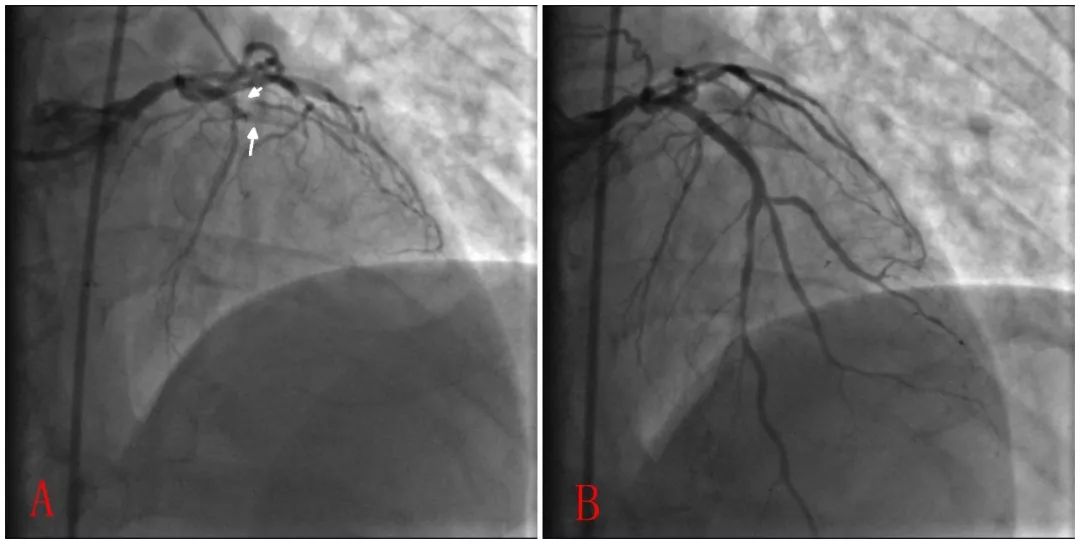

图4:2009年1月20日再次胸痛时ST段抬高;B 再次PCI术后ST回落。

图5:A 2009年1月20日术前LAD支架内血栓导致急性闭塞;B 急诊PTCA术后LAD血栓减少,血流正常。

2009年1月20日早上7:30,患者突发胸痛胸闷伴气促,心电图提示前壁ST段再度抬高明显,考虑亚急性支架内血栓形成。8:15急诊冠脉造影见LAD支架内血栓形成,完全闭塞。静脉推注8000U普通肝素和替罗非班12 ml,予以球囊扩张后血流恢复;但术中反复闭塞,故此追加了替罗非班8 ml×2次并静脉维持6 ml/L(持续48h)。最终LAD血流恢复至TIMI 3级。